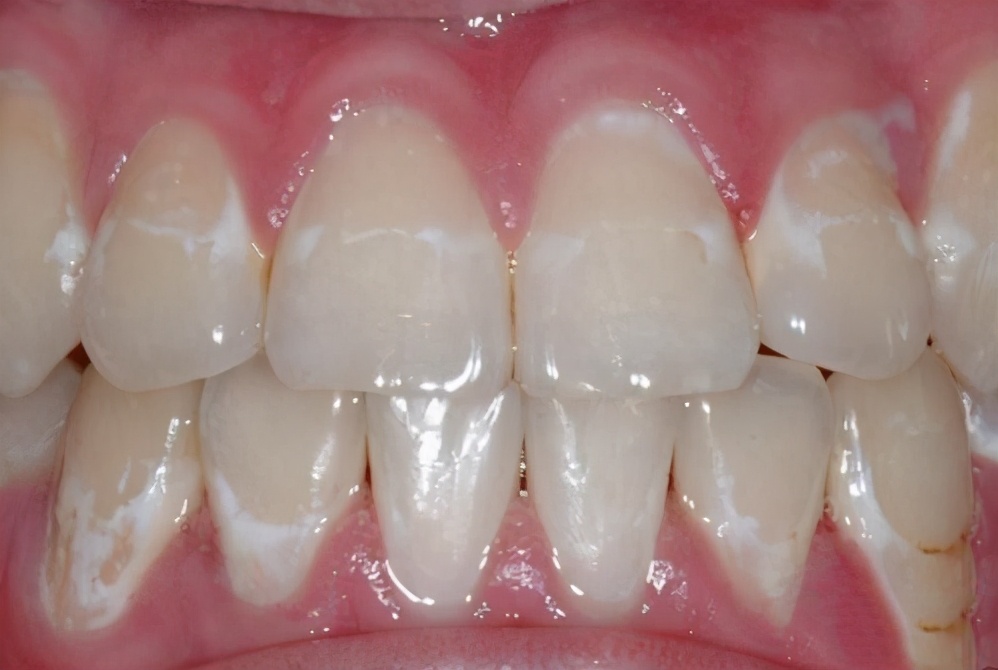

5.“牙齿出现黑线、白斑——当心蛀牙!”

上面我们讲过,咀嚼时牙疼,很可能是已经得了蛀牙。但蛀牙是有过程的,在蛀牙初期,往往都是有征兆的。比如牙齿上出现的黑线、白斑,都是蛀牙的征兆。

这种迹象,在儿童身上尤为明显。所以当爸妈们看见孩子牙齿上有黑线、白斑,建议尽快预防,以免真的出现蛀牙,到时候就只能补牙了。